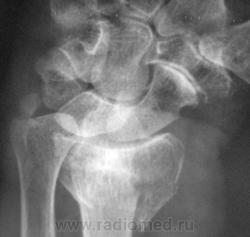

Случай 3. Пациент направлен врачом хирургом на рентгенографию лучезапястного сустава.

А вот по-поводу второго случая: перелом луча в "типичном" месте, только вот смущает ладьевидная кость - какая-то она патологическая, имеется участок разряжения костной ткани в проекции головки кости или я ошибаюсь?